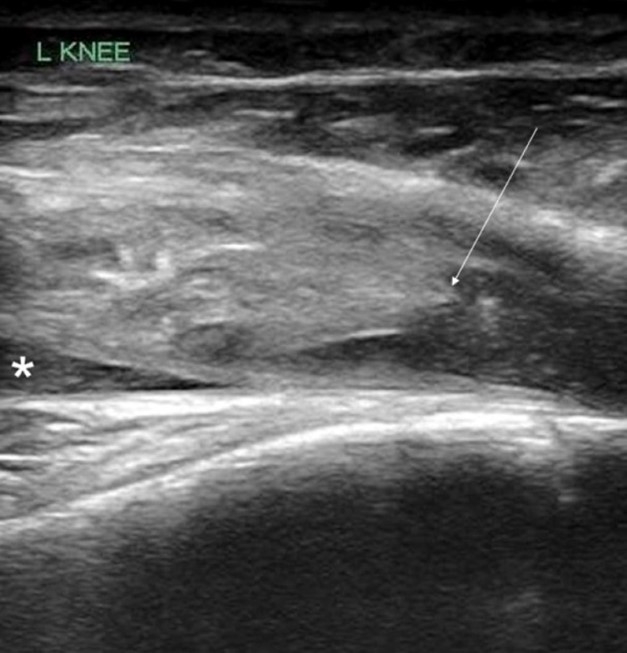

POCUS of the left knee was performed, which was concerning for a patellar tendon rupture and a joint effusion. (Figure 1 and Video 1) In addition, there was posterior acoustic shadowing obscuring part of the patellar tendon concerning for an avulsed bony fragment. (Figure 2) X-rays were performed, which confirmed the suspected diagnosis of a left tibial tubercle avulsion. (Figure 3) The patient was ultimately taken to the operating room for an Open Reduction and Internal Fixation (ORIF) by Orthopedic Surgery and discharged home the following day in a knee brace.

Figure 1. Ruptured patellar tendon (arrow) with joint effusion (*) seen in longitudinal view